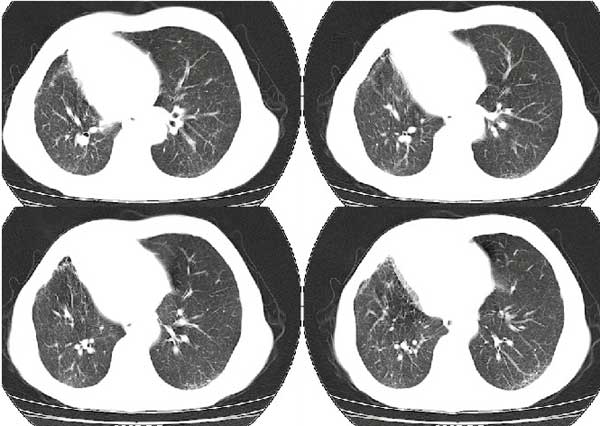

以下是引用扬仪在2005-5-12 20:46:40的发言:[br]右肺呈术后改变;双侧肺野散在分布斑片状、点状高密度病灶,(似可见“树芽征”);左上尖后段见斑团状高密度病灶(2个层面?),边缘毛糙,段性分布,与斜裂相邻,临近胸膜粘连;增强示病灶边缘强化,内呈水样密度;心影、纵隔右移,内可见4r淋巴结肿大。[br]意见:1、双肺继发性肺结核,左上为干酪病灶;[br] 2、矽肺合并感染;[br] 3、建议抗痨+抗炎。 [br]愚人之见,请高人指教!